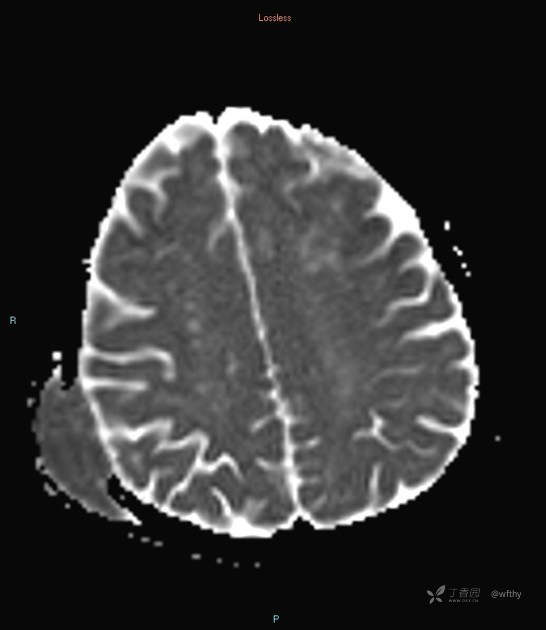

病例女65,头部肿块